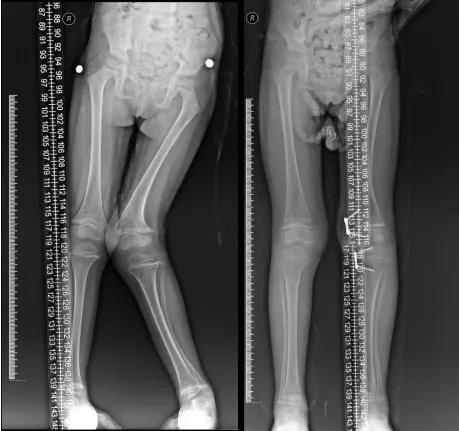

双侧僵硬型马蹄内翻足综合治疗前后

8字钢板治疗膝外翻